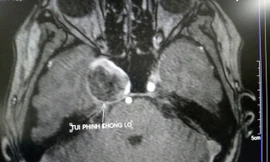

Cứu cụ bà có túi phình não khổng lồ mà không cần phẫu thuật

TPO - Một nữ bệnh nhân lớn tuổi có triệu chứng đau đầu, tê ½ mặt phải, thị lực kém, nhìn đôi nhiều tháng ròng nhưng điều trị tại bệnh viện địa phương nhưng không giảm. Sau khi nhập viện tại bệnh viện tuyến trên thì phát hiện trong não có túi phình khổng lồ, nếu không kịp thời xử trí có thể dẫn đến tử vong.